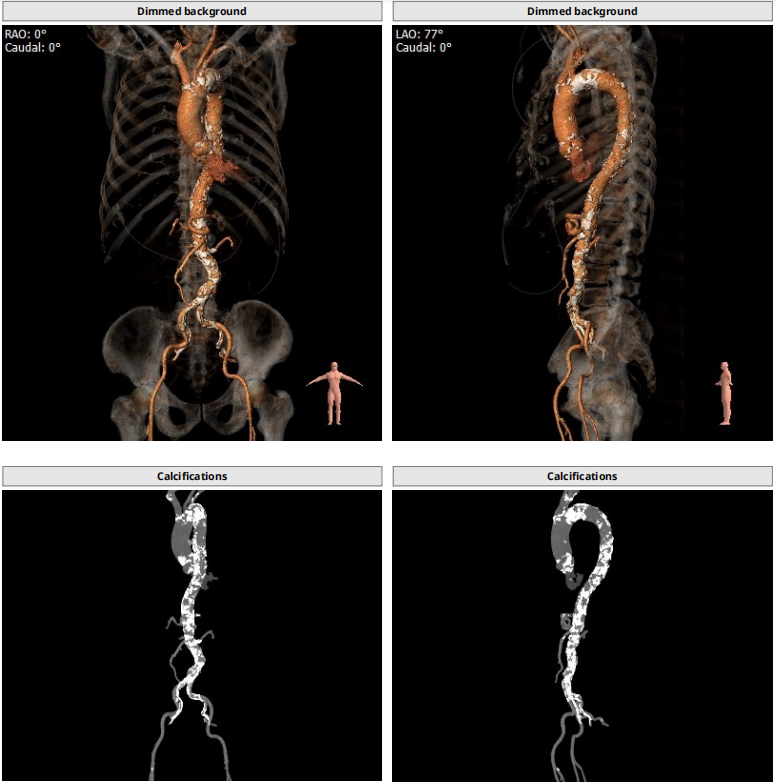

钙化积分及分布

心室大小形态

血管入路

根部CT

三叶瓣,重度钙化,钙化主要分布在瓣叶游离缘,法式窦结构较大,双冠高度较高,升主动脉未见明显扩张,心脏角度40°,左室大小可,心肌肥厚,主动脉弓部走行较平缓,主动脉弓部可见钙化,过弓轻柔谨慎,以右侧股动脉为主入路。